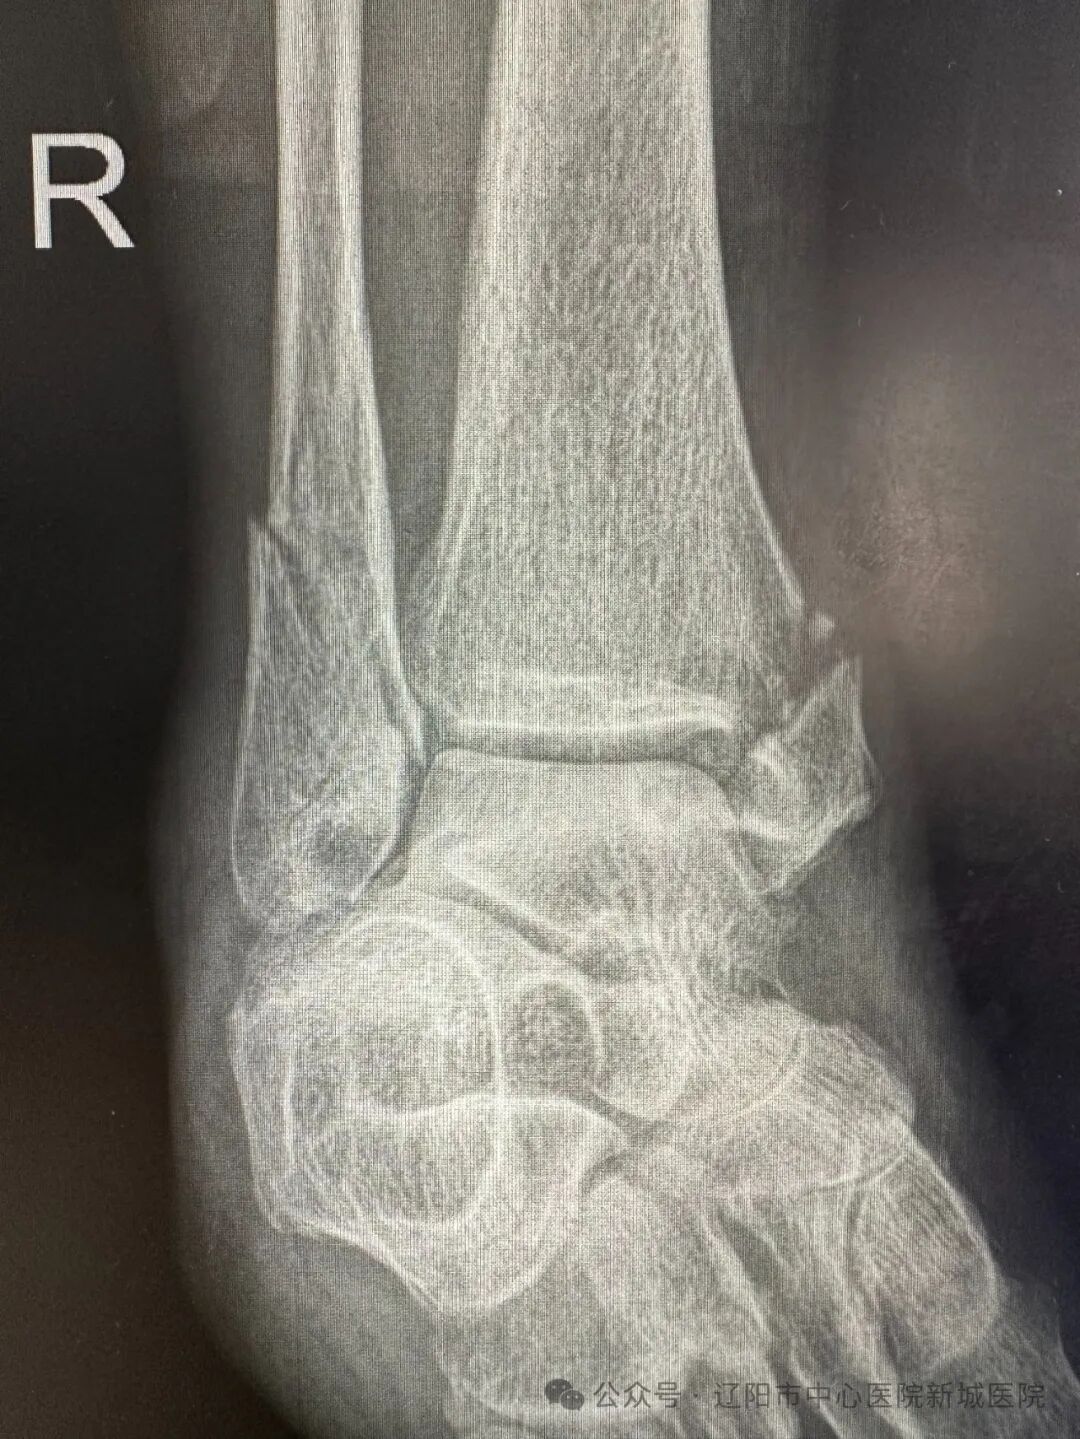

前不久,61歲的薄女士在家中不慎摔倒,當(dāng)即感覺右踝關(guān)節(jié)疼痛難忍,腫脹站不起來,休息之后未見緩解,被家人送到附近醫(yī)院行踝關(guān)節(jié)X線檢查,提示為:右踝骨折。家人非常著急,經(jīng)朋友推薦,慕名來到遼陽市中心醫(yī)院新城醫(yī)院就診,被收入骨科病房。

骨科副主任姚克勝醫(yī)生負(fù)責(zé)接診,根據(jù)薄女士的描述,詳細(xì)為患者查體,結(jié)合外院的踝關(guān)節(jié)X線片,初步診斷為:踝關(guān)節(jié)骨折。姚醫(yī)生報請骨科主任蔣剛會診,蔣剛主任帶領(lǐng)科室醫(yī)療團(tuán)隊立即對患者病情進(jìn)行評估:薄女士是右三踝骨折,骨折損傷嚴(yán)重,需立即進(jìn)行手術(shù)治療,如果治療不及時,踝關(guān)節(jié)會出現(xiàn)后遺癥,影響日后的生活質(zhì)量。姚醫(yī)生為家屬詳細(xì)講解手術(shù)指征、手術(shù)的必要性和風(fēng)險性、不手術(shù)的危害性等內(nèi)容,家屬權(quán)衡手術(shù)利弊后,同意立即手術(shù)治療。